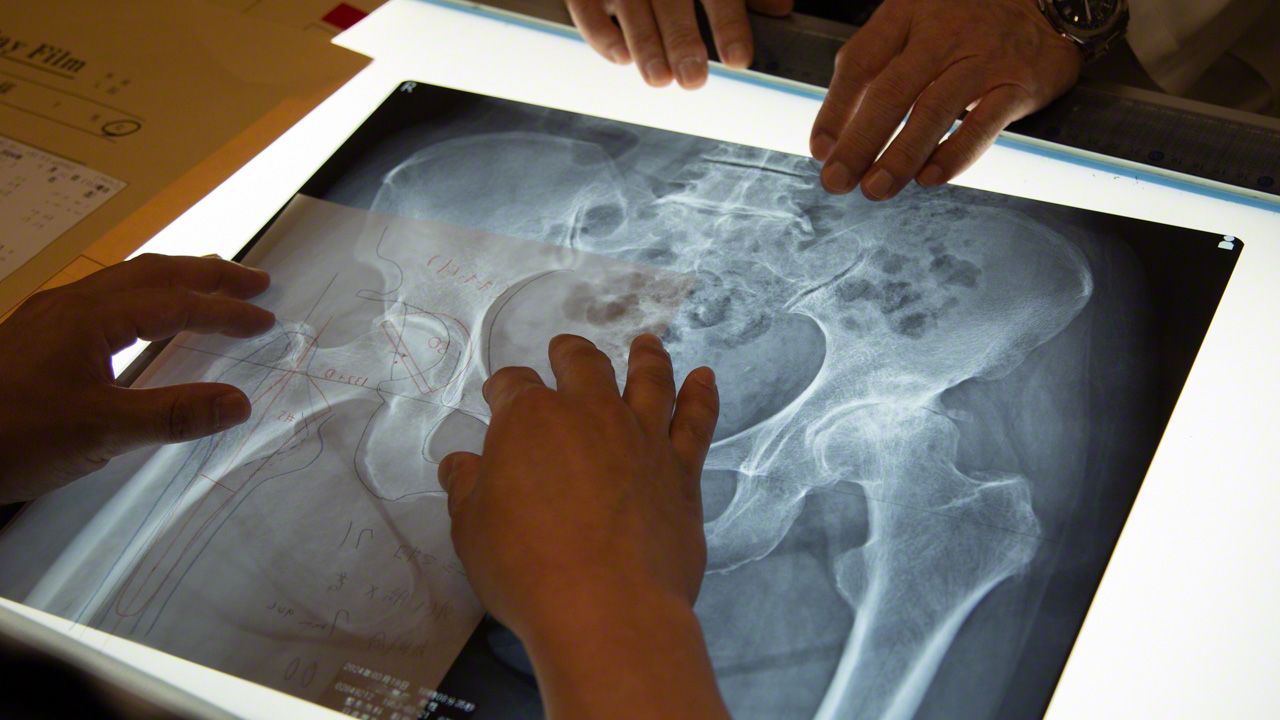

手术1周前,医生会聚集到叫“绘描室”的房间。在X光和CT等大量影像检查结果的包围中,为预定于下周做手术的患者,细致探讨最适合每个人的手术方案。

桌上放有透明胶片,上面画有各家人工髋关节厂商生产的植入关节模型。医生会把描摹纸放在上面,用铅笔按术前计划,确认植入体的植入位置。

讨论会上,医生会对照患者的各项检查数据,探讨手术方针

“我习惯骨骼用蓝笔画,植入关节用红笔画。我觉得这样看着美观,所以一直分颜色画图。但也有人只用黑笔画,每个人都不一样。”

松原医生手术当天也是早上7点就来了。他说已为自己主刀的下一个患者,绘制了术前计划。

髋关节中心为做术前计划,已斥资引入了3D导航软件,手绘轨迹图并非必须。但是,一边试错一边画线,这一操作可当作术前的模拟预演,对手术经验尚为不足的年轻医生来说,是一种形象思维训练。每当此时,也必须由松原医生最终拍板。

使用蓝、红铅笔、分度器和直尺,活动自己的双手,在脑海中预演手术过程

松原医生强调了形成肌肉记忆的意义,他说:“老医生都跟我们说‘在动手画图的过程中,骨骼后面的组织关系,还有看不见的线,就都能慢慢看清楚了’。我年轻的时候,还没有3D技术。我从30年前起就是这个风格了。”